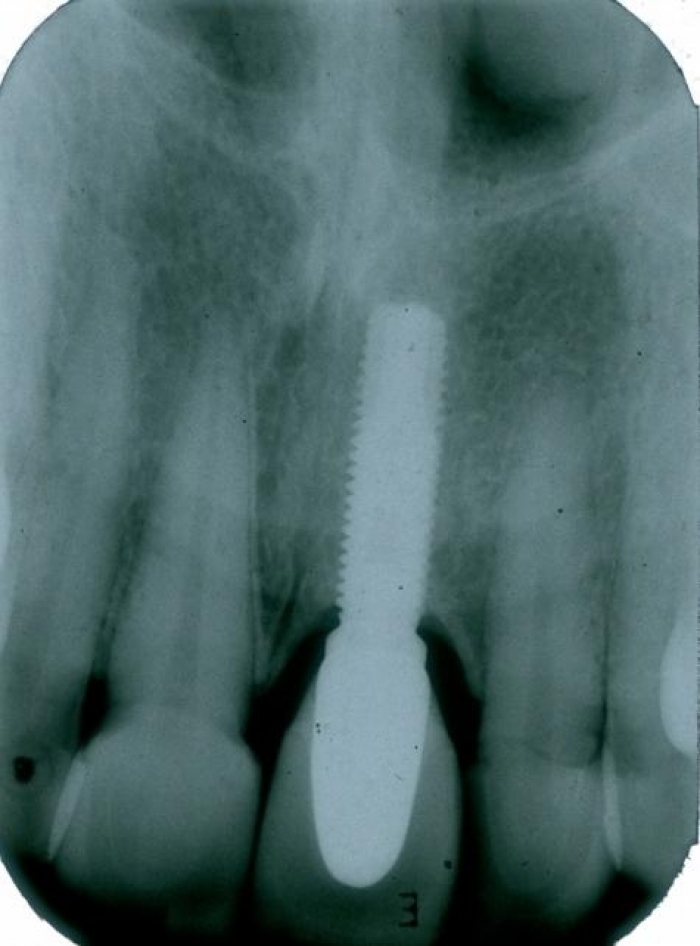

Raio X de 15 meses de controle